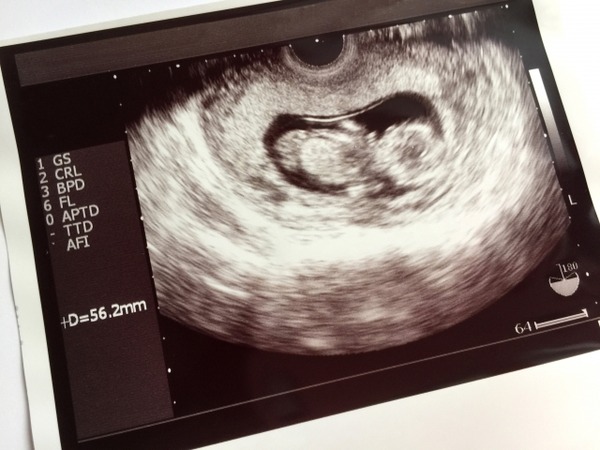

【悲報】嫁ちゃん(38)、「ダウン症を妊娠したみたい…」結果・・・。 Twitter Facebook はてブ LINE コピー 2022.03.26 スポンサーリンク 1: 風吹けば名無し 2020/12/01(火) 14:27:43.70 ID:vudapw3/M ワイは堕ろせって言ってるが嫁ちゃんは誤診で正常かもしれなから産みたいだとさ 続きを読む